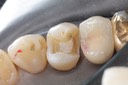

Alan Chinn #28 pre-op

Alan Chinn #28 caries removal